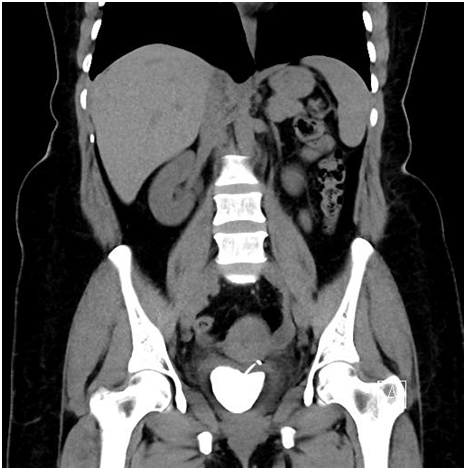

On initial evaluation with ultrasound (Figure 1) revealed a vesical calculus. On further evaluation with X-ray KUB (Figure 2) and CT Scan (Figure 3) (Figure 4) showed large laminated vesical calculus and Copper T seen outside the uterus with horizontal portion in the vesicouterine pouch, long vertical portion seen protruding into the urinary bladder lumen through the posterior wall partly encased in the vesical calculus.

Figure 3 CT showing Calculus and vertical limb of Cu-T.